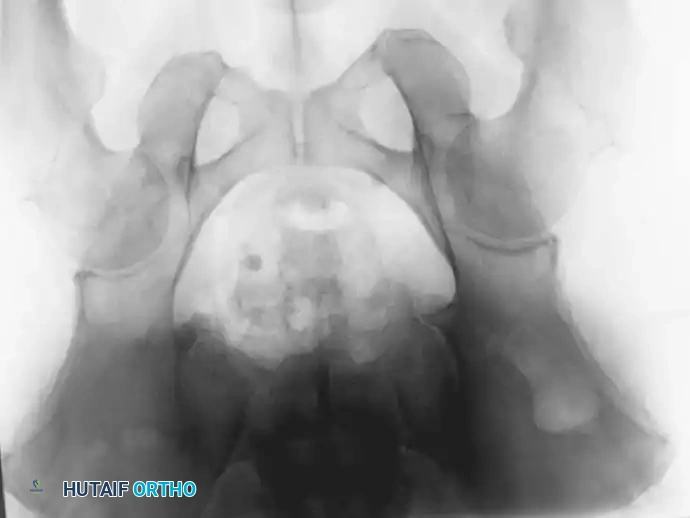

Fig. 22-23: (A, B) Radiograph and CT of a 66-year-old man with metastatic lung cancer destroying the right acetabular posterior column and wall. Preoperative embolization was performed to minimize blood loss. (C) Intraoperative view after curettage. Guidewires were placed from the defect to the posterior ilium and anterior iliac crest. Cannulated screws were placed over the wires to support the cement mantle. (D) An acetabular cage was placed, and the defect was filled with PMMA as the cup was cemented. (E) Postoperative radiograph demonstrating a stable construct.